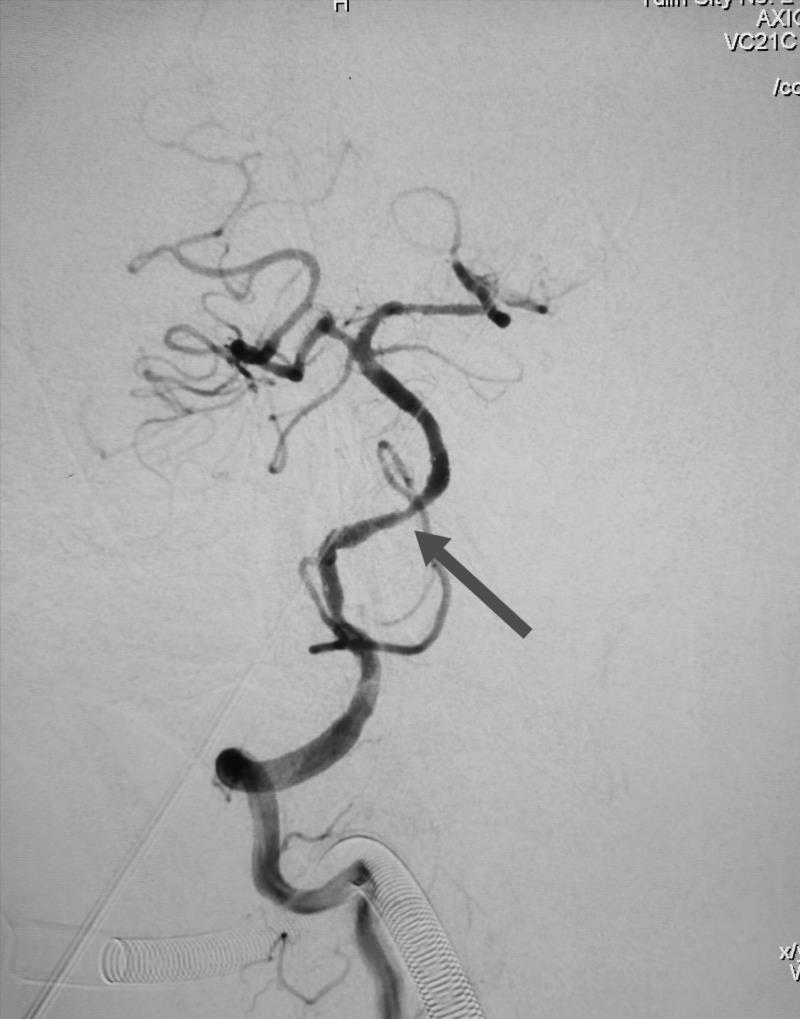

椎基底动脉重度狭窄

经全脑血管造影术,发现患者右侧椎动脉V4段重度狭窄,正是病灶责任血管,同时发现右侧颈内动脉起始段重度狭窄。患者王某的情况岌岌可危,这两处血管狭窄随时可能闭塞,一旦闭塞,轻则出现严重残疾,完全丧失生活能力,重则很快危及生命,他的椎动脉远端狭窄处介入手术风险异常高,手术过程中很可能发生急性血管破裂或栓塞,形成严重的脑干出血或者梗死,造成死亡。患者右颈内动脉狭窄处于颈动脉窦部,是人体血压和心率的感应器,非常敏感,加之该患者平时就有心率缓慢的情况,术中很有可能心脏停搏造成死亡。